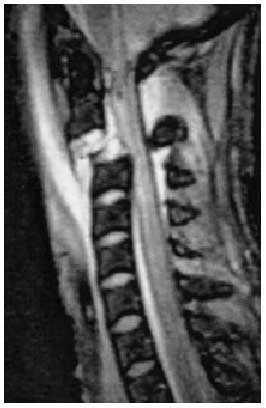

Paciente que sufrió accidente de tráfico (colisión directa entre automóvil y camión) con paro cardiorrespiratorio inmediato que precisó maniobras de reanimación y ventilación mecánica con Glasgow de entrada de 3. Se trasladó a un hospital cercano, donde se realizó un examen radiológico inicial (fig. 1) que mostró fractura-luxación de vértebras C2-C3. Se inició bolo de metilprednisolona, descartándose otras lesiones vitales, siendo trasladada posteriormente al hospital de referencia para valoración y tratamiento definitivo. Se efectuó tomografía axial computarizada (TAC) de cráneo y resonancia nuclear magnética (RNM) cervical (fig. 2), evidenciándose la fractura de C2 con luxación de C2-C3 que condiciona compresión del canal medular a dicho nivel. La paciente ingresó en la UCI. A los pocos días se realizó reducción quirúrgica de la luxación y fijación posterior mediante cerclaje alámbrico, realizándose 4 días después fijación de C2-C3 por vía anterior mediante placa de osteosíntesis.

Fig. 2.